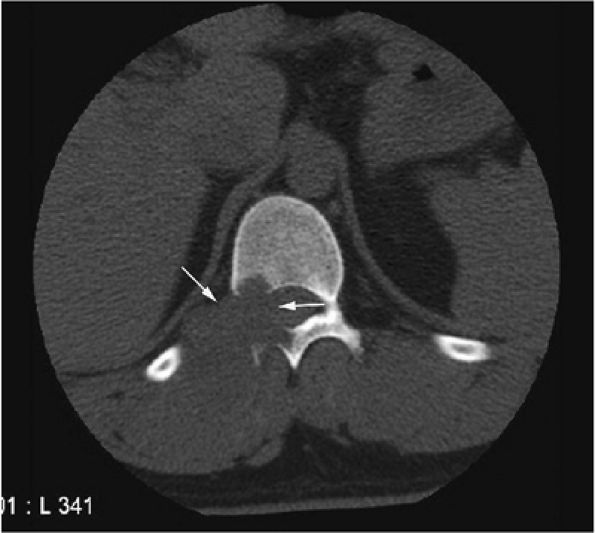

FIGURE 14-78 ● (A and B) Axial CT images showing a large chondrosarcoma arising from the left superior pubic ramus. Punctate calcifications (arrows) are well visualized on the CT images. T2-weighted sagittal (C) and axial (D) images show a large heterogeneous cartilage tumor arising from the left pubic ramus. (E) Axial fat-suppressed T1-weighted contrast-enhanced image shows enhancement in a ring and arc septal pattern.